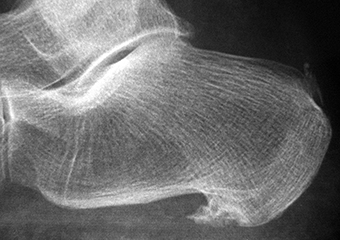

La apariencia anatómica es variable y se han clasificado en espolones sencillos e irregulares. El espolón sencillo es una estructura triangular que termina con una punta afilada, con una cortical ligeramente esclerótica y trabéculas bien desarrolladas. En contraste, los espolones irregulares tienen los bordes mal definidos y la trabeculación es poco clara y se producen cuando hay un fuerte proceso inflamatorio [52] (Figura 3).

Figura 3A

Figura 3B

Figura 3C

Figura 3. A, B, C) Imagen radiográfica de espolones del calcáneo.